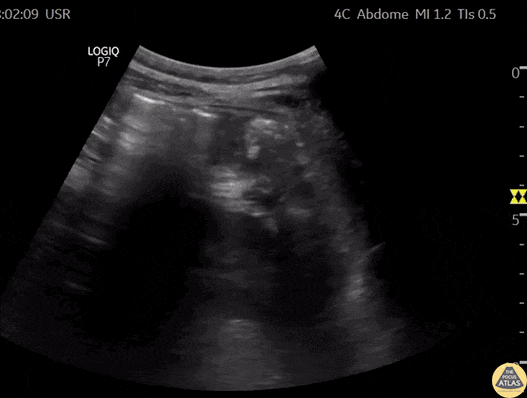

Biliary - Thick Walled Gallbladder in Dengue Fever (Short Axis) [2/2]

A 28 year old female comes to the ER with fever, myalgia, hypotension, and abdominal pain. This case illustrates one of the ultrasound findings in Dengue Fever in the Leakage Syndrome Stage. We can see a large, thick-walled gallbladder and the presence of pericholecystic fluid. This clip demonstrates the gallbladder in short-axis view. Contributor: Renato Tambelli (@R_Tambelli @JediPocus)